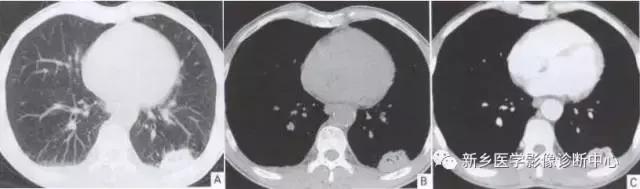

单发胸膜间皮瘤

常发于胸壁腋缘,单发、多发良性,无症状或局部钝疼。圆形或半球形密度影,基底位于胸膜,与胸壁成钝角,密度均匀。

4个不同的胸膜间皮瘤: